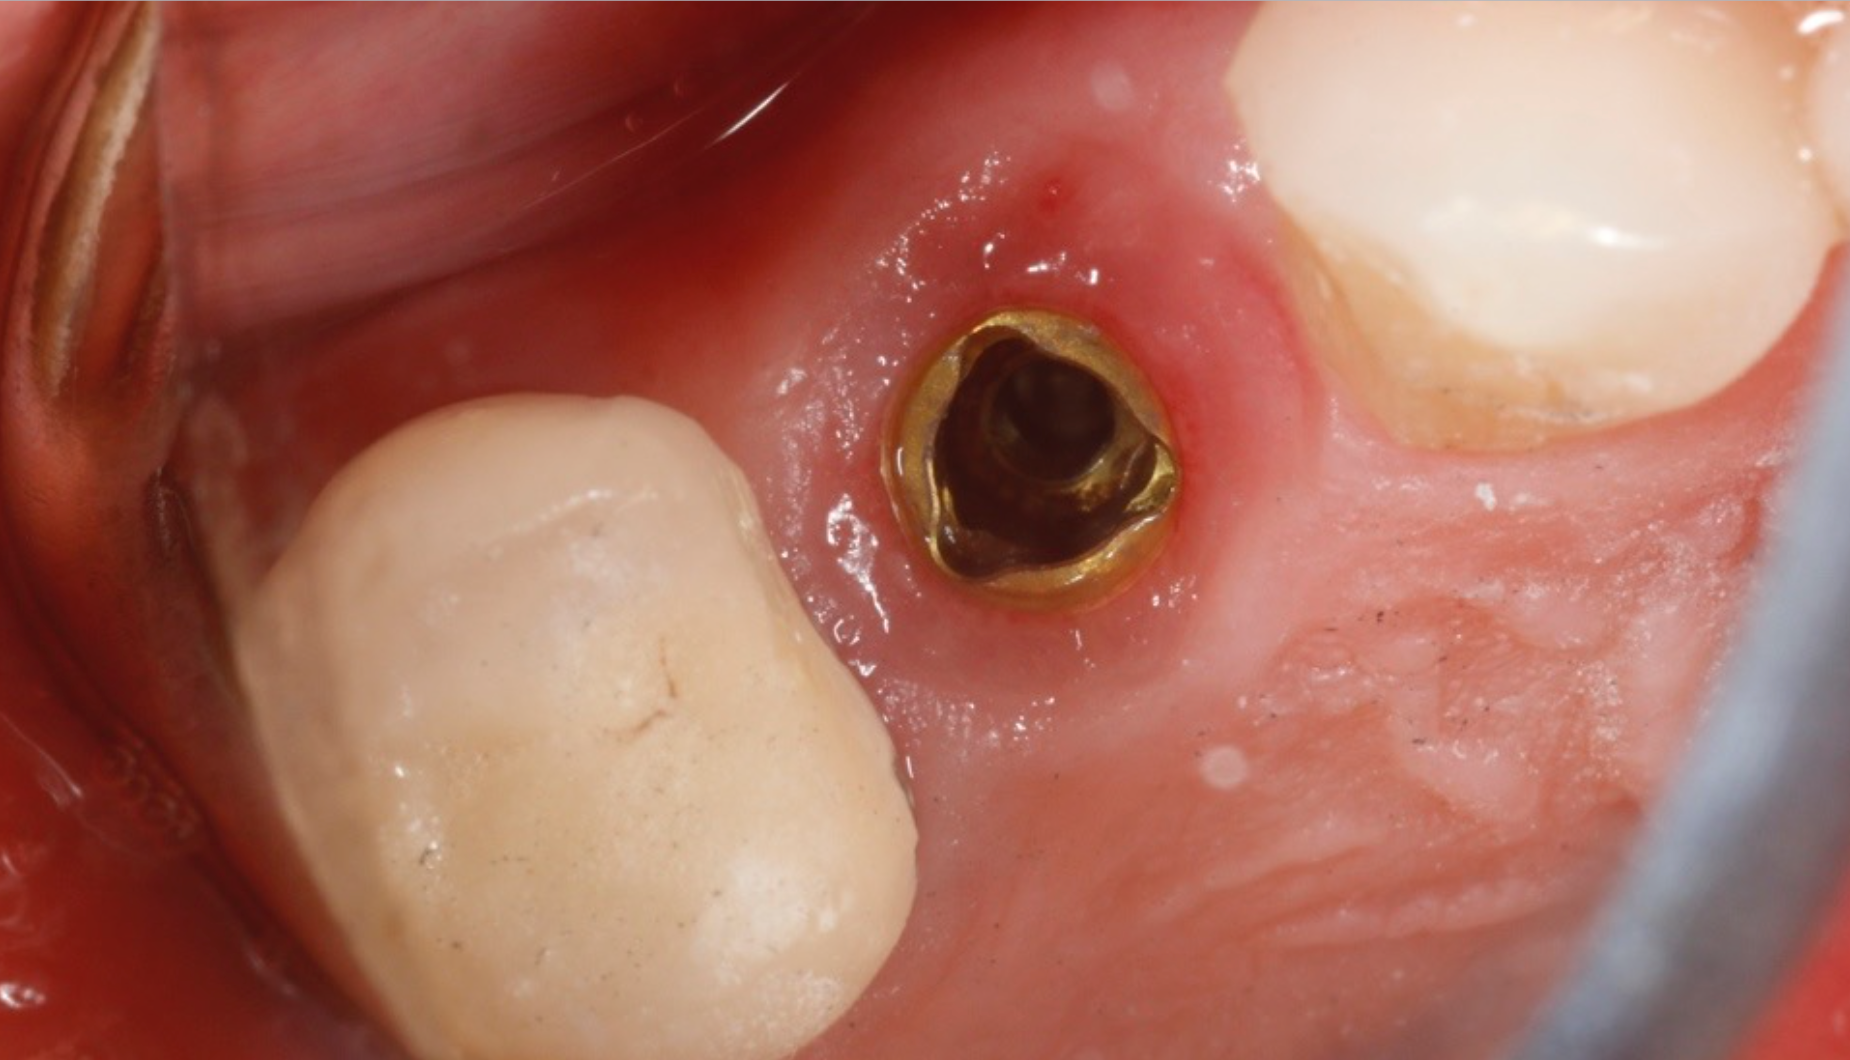

The implant in the tooth #12 area on the 50-year-old female patient is ready for restoration. In this instance, a stock abutment was selected and prepared extraorally. The abutment was placed to 25 ncm torque.

The PlanmecaFit with the Planmeca Emerald™ scanner (Figs. 7-8) was used to take a set of digital impressions, and the restoration was milled in the PlanMill® 40 S using an Ivoclar Vivadent IPS e.max block shade A1.